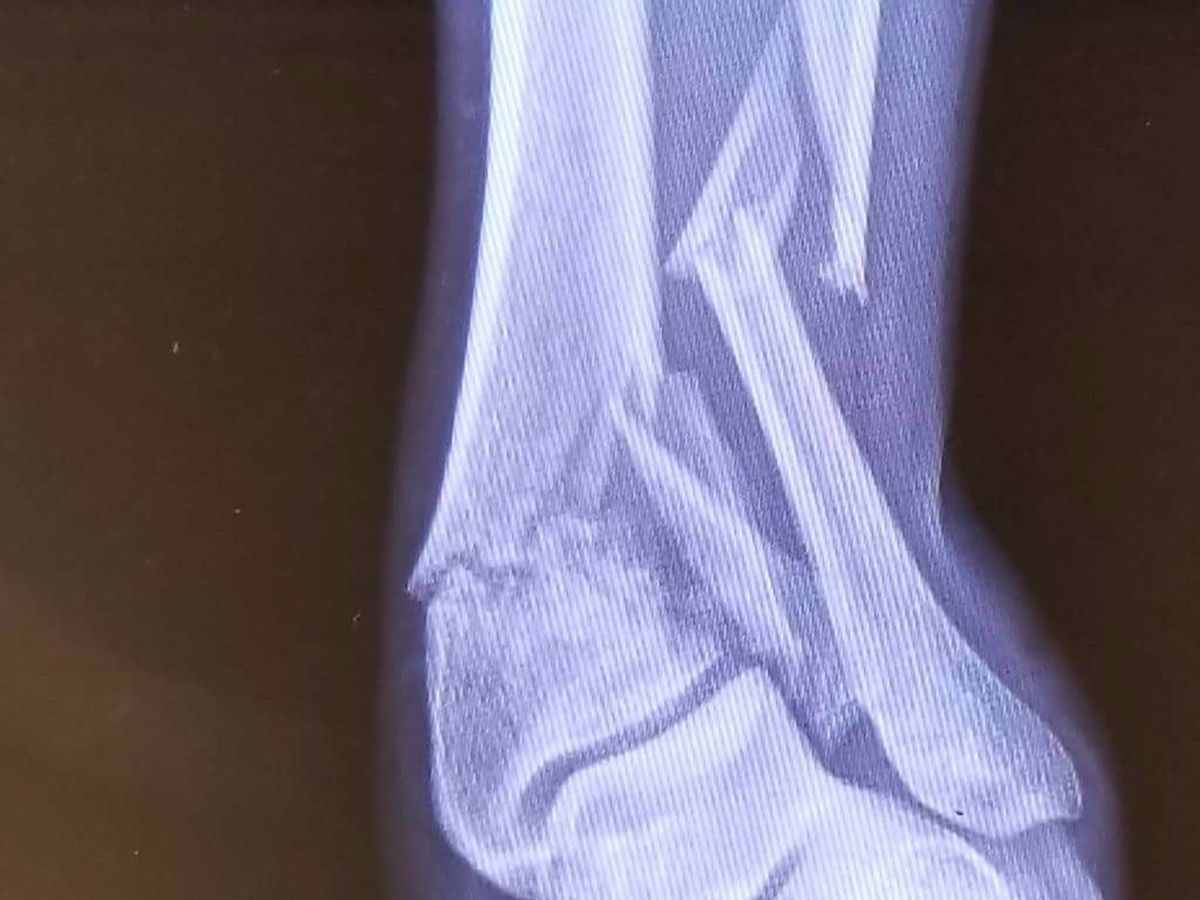

On July 20, our plans for the next several months were ruined when I had a 200 pound piece of equipment fall after a safety latch failed. I was kneeling underneath, putting a large gash in my leg and breaking the ends of my tibia and fibula on my left leg, just below my ankle. Over the next couple days, its become more and more clear the future repercussions this is going to have on our daily lives. We have to get my wife her license, her name on insurance, continue to pay bills for electric, internet and phone service as well as the car payment. If we raise enough, we're hoping to get her some time off to help me as I go through the next few rounds of surgery and physical therapy. Anything you could contribute will help to support us and our 4 children as we focus on making it through this sudden difficult time.